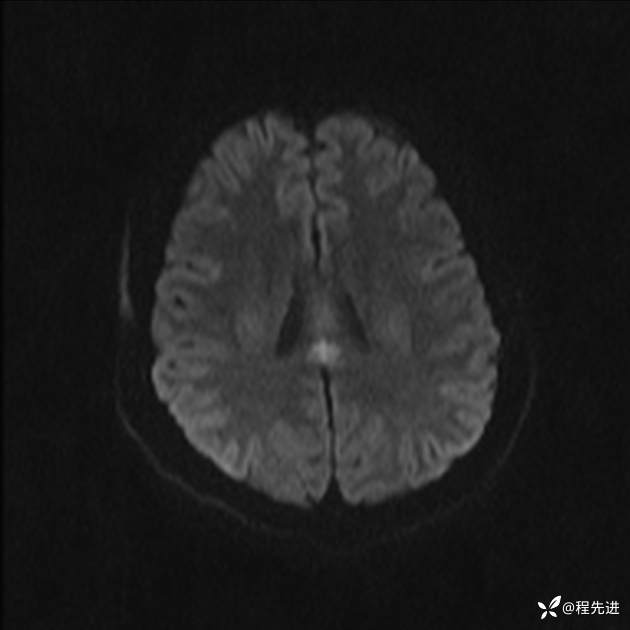

【患者信息】:女,25岁

【现病史及既往史】:言语含糊、意识状态改变1天。有下段剖宫产术10天病史。

【检查】